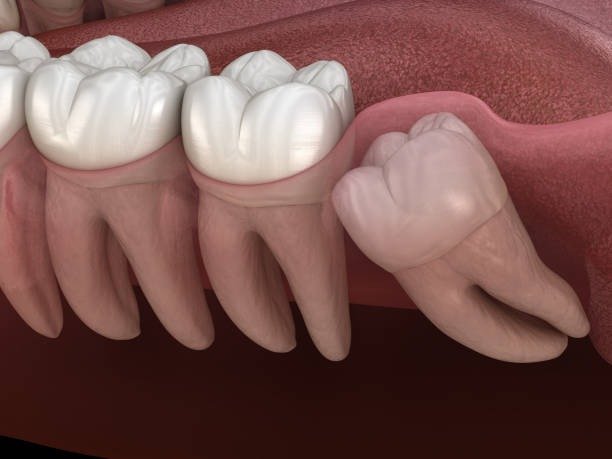

Wise are extracted through an operation, that is through a surgical process, where the tissues of the mouth and often the bone have to be cut. Consequently, the recovery process is important to minimize incidences such as infection or dry socket, which is a painful condition whereby the clot formed in the tooth socket is dislodged, thereby, releasing the nerves and bones seated at the bottom of the socket.

- First 24-48 hours: The first stage is when clot forms on the surface of the extraction site. Coagulation is essential to achieve normal healing in the body.

- Days 3-5: Normally, swelling and discomfort are expected at this phase of the recovery process. It forms scar tissue, but the scar is still fragile and easily damaged.

- First week: You are not quite better by the end of the week, although the primary stage of healing will have taken place.

- Weeks 2-3: How.long does it take to see deep healing of the tissues and the bone, and your gums might still be quite sore.

- 1 month+: Healing is prolonged but by this time most of the patients are experiencing very little pain and are ready to return to their daily activities.